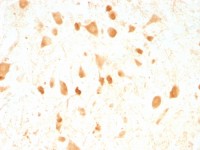

IHC-P analysis of human liver carcinoma (A), recturn carcinoma (B), normal medulla tissue (C) and normal interbrain tissue (D) using GTX83081 TIP60 antibody [3F9].